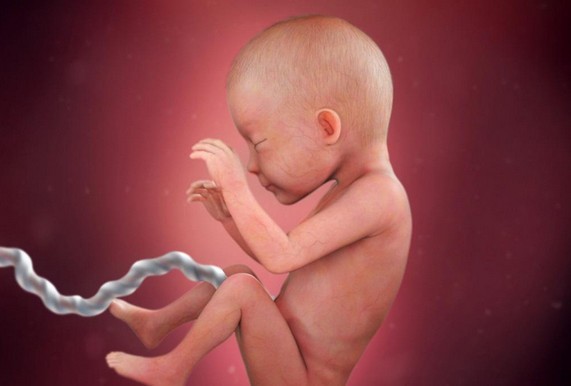

الأسبوع الثلاثون

خلال الأسبوع الثلاثون يكتمل نمو شعر الجنين وتزداد لديه القدرة على فتح عينيه بشكل أكبر ويتم إنتاج خلايا الدم الحمراء في النخاع العظمي ويصبح وزن الجنين بنهاية هذا الأسبوع كيلو و300 جرام.